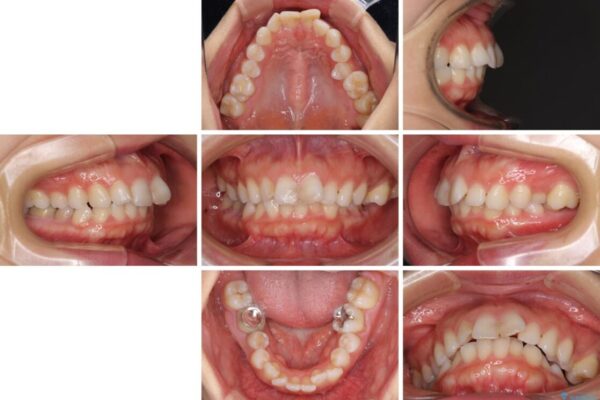

口元の閉じにくさと、奥歯の咬み合わせを気にして来院された患者様です。

治療計画

左下の大臼歯2本が顕著に舌側に傾斜しているため、まずは奥歯の咬み合わせを改善をし、その後上下左右の第1小臼歯4本を抜歯することで口元を引っ込めながら整えることとしました。

治療後について

奥歯の咬み合わせ改善には1年ほどの期間と処置中の噛みにくさを強いることとなりましたが、抜歯後はスムーズに治療を完了させることができました。

歯ぎしりの際に奥歯が干渉していた咬み合わせも理想的な状態に改善できました。